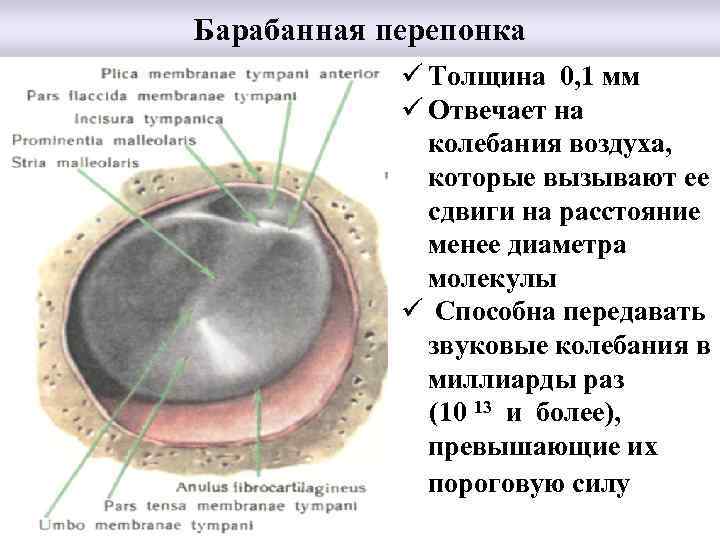

Барабанная перепонка ü Толщина 0, 1 мм ü Отвечает на колебания воздуха, которые вызывают ее сдвиги на расстояние менее диаметра молекулы ü Способна передавать звуковые колебания в миллиарды раз (10 13 и более), превышающие их пороговую силу